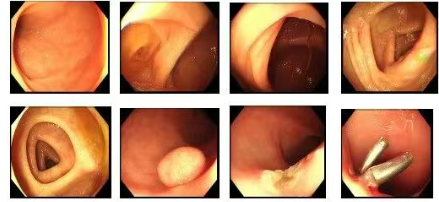

45岁的孙女士因便秘就诊,在家人劝说下为排查便秘原因接受肠镜检查,结果在直肠发现一枚肿瘤,病理确诊为神经内分泌瘤。幸运的是,因发现得早,已行内镜下切除,由于切除完整,切缘干净,评估后任务无需追加外科手术,定期密切随访即可。

医生:李女士是“早筛受益者”的典型。肠镜是发现结直肠癌的最有力手段。建议40岁以上人群,尤其有家族史或长期肠道症状者,定期进行肠镜检查。

45岁的张先生因排便困难入院。肠镜检查中发现肠腔可见肿物,病理确诊为恶性肿瘤。瘤体较大,已错过了肠镜手术的最佳时机,遂行腹腔镜手术,术后恢复顺利。

幸运的是,因为发现得早,肿瘤分期属于非常早期。经过腹腔镜微创手术,恢复得很快,且术后病理显示无需化疗,定期复查即可。

医生:许多结直肠癌由息肉演变而来,过程可长达5-10年。发现并切除息肉,就是阻断癌变的关键一步。排便困难是重要信号,切勿当成便秘而忽略。